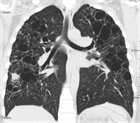

1. 肺LCHの診断には、胸部CT検査(HRCT)は必須である(推奨度1)